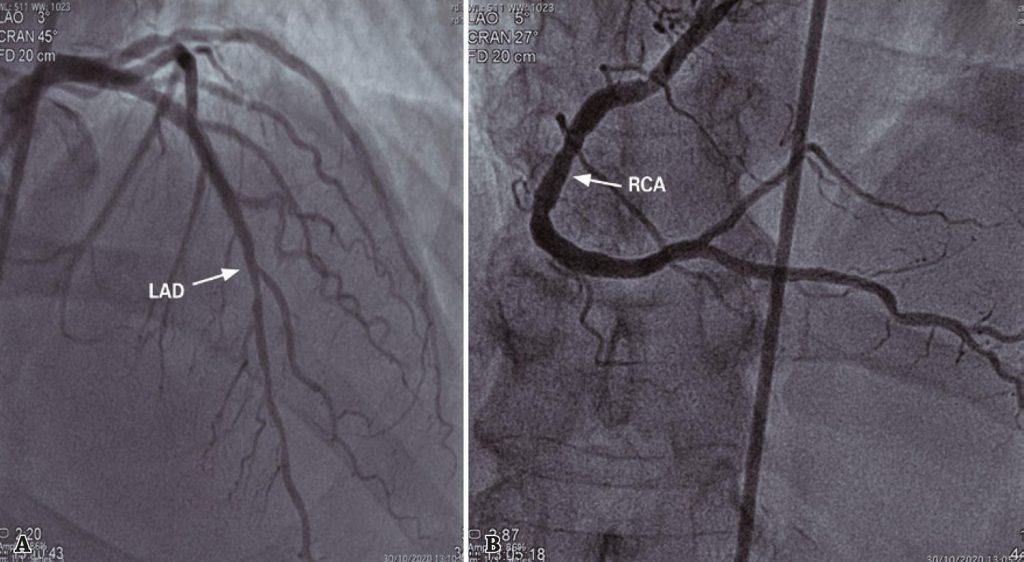

Figure 4

Cardiac catheterization of October 30, 2020. (A) Absence of significant lesions in the left anterior descending artery. (B) Absence of significant lesions in the right coronary artery.